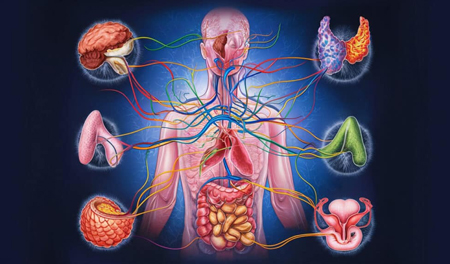

Identifying and treating hormonal imbalances that affect fertility.

Restoring ovulation and enhancing conception potential through customized treatments.

Preconception and prenatal genetic assessment to ensure healthy pregnancy outcomes.